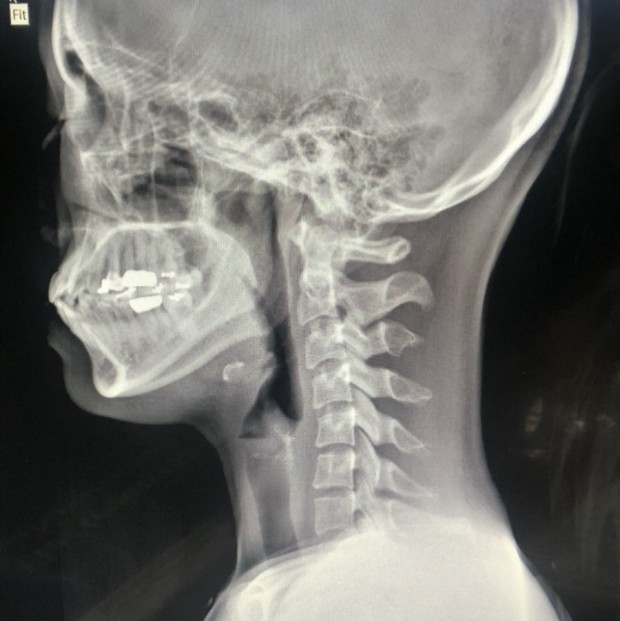

오늘은 목 건강을 위협하는 질환, **목디스크(경추 추간판 탈출증)**의 증상에 대해 이야기하려 합니다. 목디스크는 목뼈 사이에 있는 디스크가 제자리를 벗어나 신경을 압박하면서 발생하는 질환입니다.

목디스크는 목 통증뿐만 아니라, 신경 압박으로 인해 신체의 다른 부위에도 다양한 증상을 유발합니다. 다음은 목디스크 환자들이 흔히 겪는 10가지 주요 증상입니다.